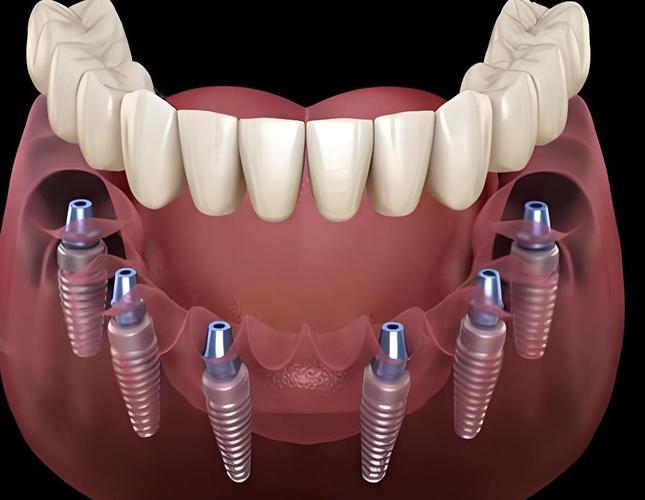

all-on-4植牙技术是针对半口或全口牙缺失患者的高效种植修复方案,其核心通过植入4颗特殊角度的种植体,支撑整个上颌或下颌的牙列修复,而“all-on-4植牙图”则直观展示了这一技术的关键设计逻辑、手术流程及修复结构,帮助患者理解从术前规划到术后效果的全过程。

all-on-4植牙图通常包含术前设计、术中植入、术后修复三个阶段的示意图,重点突出种植体的分布、角度及力学传导机制。

植牙图中,4颗种植体的分布是技术核心:前牙区(侧切牙位置)植入2颗种植体,通常垂直于牙槽骨,提供初期稳定性;后牙区(磨牙位置)植入2颗种植体,以30°-45°角度倾斜植入,这种设计有两个关键作用:一是避开上颌窦(上颌后牙区)或下牙槽神经管(下颌后牙区)等重要解剖结构,避免植骨手术;二是利用倾斜角度增加种植体与骨组织的接触面积,并通过力学分散咬合力,减少种植体承受的杠杆力,提升长期稳定性。

基台与牙冠的连接方式

植牙图中可见,种植体上方通过基台连接固定桥牙冠,前牙区垂直种植体通常使用直基台,后牙区倾斜种植体则使用角度基台(如17°或30°基台),确保基台长轴与牙冠长轴一致,避免侧向力损伤种植体-骨结合界面,牙冠部分多采用全瓷材料(如氧化锆),通过CAD/CAM技术精准制作,形态、颜色与自然牙高度匹配,植牙图中会标注咬合接触点的位置,确保前牙轻接触、后牙多点均匀受力,实现功能与美观的统一。